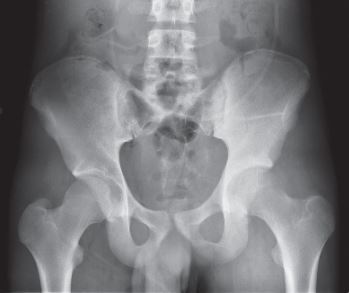

You will be monitored periodically with X-rays over the course of 5 years. Sometimes an MRI and/or CT may be used to additionally monitor the area to make sure the tumor has not come back. You will then have follow up appointments every 4 months for the first 2 years, then every 6 months for the next 2 years, and then once a year. Since the bone integrity has been restored to full or almost full, recovery is anticipated provided the patient adheres to strict physical therapy.